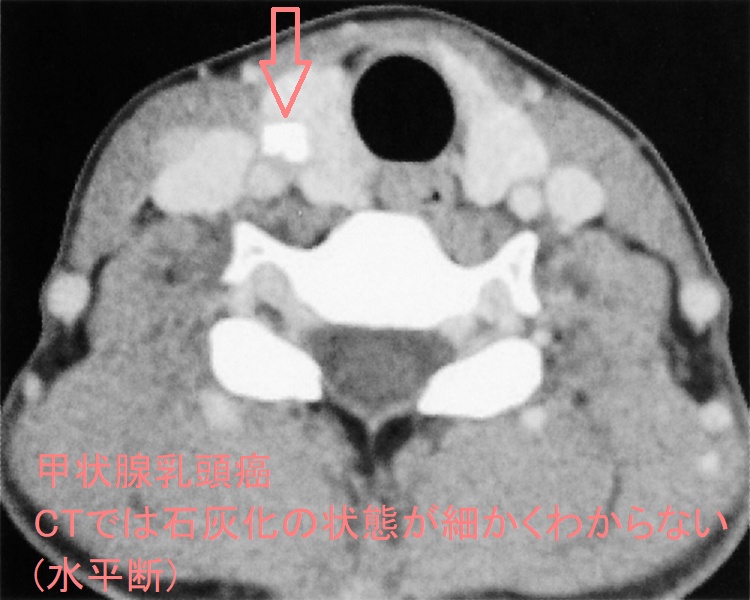

- 精密でも5mm、通常10mmスライスで撮影するため、解像度が悪く、5-10mm以内の病変が写らない確率が高い[甲状腺超音波(エコー)検査は、3mm大(条件次第では2mm大)の甲状腺癌でも見つかります。また、甲状腺乳頭癌において最大の特徴である微細な砂粒状石灰化(psammoma body)は5mm未満のため、CT・MRIでは写りません。]

同時に、CTでは甲状腺癌の微細石灰化(5mm以下)が写らない。さらに、細かい石灰化の状態を評価できない。